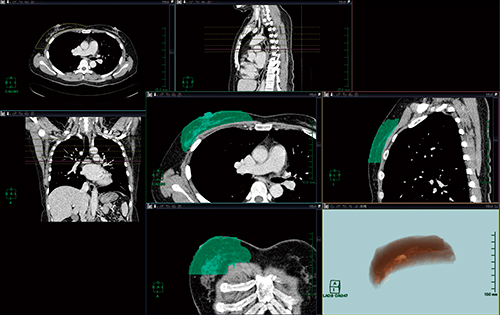

次に,皮弁として使用する広背筋を,乳房の切除領域抽出と同様の手順で抽出し(図4 a,b),体積を測定する(図4 c)。この値を広背筋皮弁体積((2))とした。また,このレイヤーも保存した。

図4 広背筋皮弁領域の設定

a,b:広背筋皮弁領域の位置関係

c:広背筋皮弁領域の体積測定(測定値230.12mL)